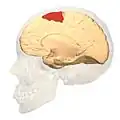

Brodmann area 6 (BA6) is part of the frontal cortex in the human brain. Situated just anterior to the primary motor cortex (BA4), it is composed of the premotor cortex and, medially, the supplementary motor area (SMA). This large area of the frontal cortex is believed to play a role in planning complex, coordinated movements.

Brodmann area 6 is also called agranular frontal area 6 in humans because it lacks an internal granular cortical layer (layer IV). It is a subdivision of the cytoarchitecturally defined precentral region of cerebral cortex. In the human brain, it is located on the portions of the precentral gyrus that are not occupied by Brodmann area 4; furthermore, BA6 extends onto the caudal portions of the superior frontal and middle frontal gyri. It extends from the cingulate sulcus on the medial aspect of the hemisphere to the lateral sulcus on the lateral aspect. It is bounded rostrally by the granular frontal region and caudally by the gigantopyramidal area 4 (Brodmann, 1909).[1]